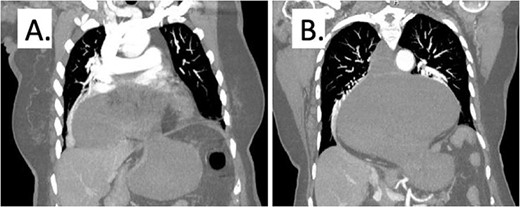

On presentation to the hospital, she was noted to have nausea and coffee-ground emesis, and she was complaining of pain in her chest and epigastrium. A computed tomography scan of the chest, abdomen, and pelvis revealed a large hiatal hernia with the gastroesophageal junction in the mid-chest, marked distension of the gastric lumen secondary to volvulus (Fig. 1). The cardiac workup was negative. A nasogastric tube was placed for decompression. Her labs were notable for a lactic acid of 4.1 mmol/L (0.5–2.0 mmol/L) which increased to 4.3 mmol/L even after adequate fluid resuscitation. She developed persistent tachycardia, was febrile to 38.4 C, and began having mental status changes. She was taken emergently to the operating room at this time.

Representative computed tomography image demonstrating gastric distention and area of volvulus (A) and extent of hiatal hernia (B).